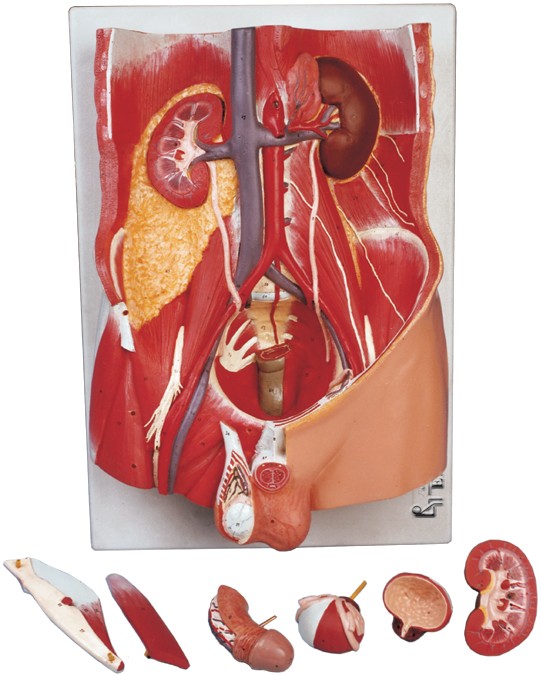

مولاژ کلمه ای فرانسوی به معنای قالب است. آناتومی بدن انسان با تجهیزاتی مانند مولاژهای پزشکی یا کالبدشناسی که نمونه هایی تخصصی و شبیه به اندام های بدن انسان هستند، به دانش آموزان و دانشجویان آموزش داده می شود. استفاده از مولاژ در روند یادگیری و آموزش تاثیر به سزایی داشته و تمامی اندام ها را با تمامی جزئیات و با کیفیت بالا می توان مشاهده و بررسی کرد. مولاژها عموما از جنس PVC نشکن، لاستیک یا فوم ساخته شده و دارای رنگ طبیعی و قابل شست و شو هستند. برخی از انواع مولاژها مناسب برای آموزش مراقبت های پزشکی و پرستاری است و امکان تمرین بانداژ، تزریق، CPR، جراحی و... وجود دارد. مولاژها معمولا هر کدام عضوی از بدن را نمایش می دهند و قابلیت تفکیک و مشاهده همه بخش های آن وجود دارد.

مولاژها معمولا با توجه به نوع اعضا و یا دستگاه های بدن در اندازه طبیعی، کوچکتر و یا چندین برابر بزرگتر ساخته می شوند تا امکان مشاهده دقیق اجزای آن ها فراهم شود. برخی مولاژها از چندین قطعه ساخته شده اند که قابلیت تفکیک دارند. علاوه بر نمایش ساختار و نحوه عملکرد اعضای بدن، ماهیچه ها و عضلات بدن را نیز می توان به کمک مولاژها مشاهده کرد.

مولاژها ابزاری تخصصی برای آموزش دانشجویان پزشکی، دندان پزشکی، پرستاری و مامایی است. همچنین در مدارس و سایر مراکز آموزشی میتوان از انواع مولاژها برای بهبود یادگیری و آموزش بهره برد. در کلینیک های زنان و زایمان، دندان پزشکی، سالن های تشریح، بیمارستان ها و آزمایشگاه ها نیز مولاژهای مراحل حاملگی، انواع دندان و بیماری های آن کاربرد دارند.